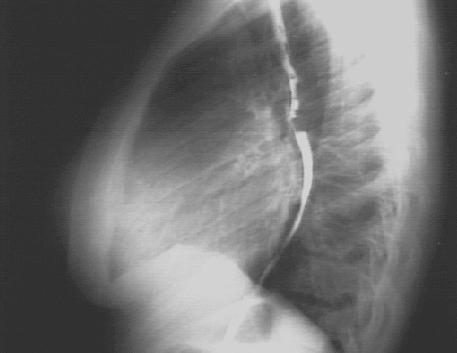

The lateral view with barium swallow, demonstrates posterior displacement of the esophagus by the markedly enlarged left atrium.